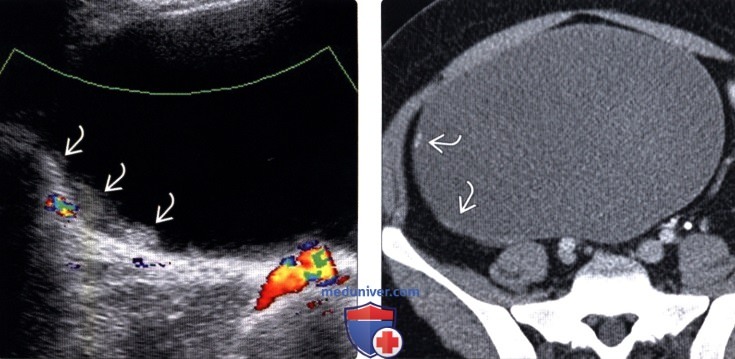

В процессе гинекологического УЗИ точно устанавливаются размеры кистомы, толщина капсулы, уточняется наличие камер и сосочковидных разрастаний. При пальпации живота, а также с помощью УЗИ брюшной полости может выявляться асцит. Обнаружение опухоли яичника требует исследования онкомаркера СА-125. В ряде случаев для уточнения диагноза целесообразно проведение КТ или МРТ малого таза. Окончательное подтверждение диагноза и выяснение морфологической формы папиллярной кистомы яичника производится в процессе диагностической лапароскопии, интраоперационного гистологического исследования.

Трансвагинальное УЗИ обычно дает гораздо более точную оценку поражения, чем трансабдоминальное, особенно при поиске кровотока.

Васкуляризация, продемонстрированная в твердой области, сосочковой проекции или в перегородке, вызывает беспокойство. Васкулярность измеряется с помощью цветного или энергетического допплера.Исторически использовался индекс резистентности (RI) с уровнем ниже 0,4, который считался высоким риском злокачественных новообразований, но больше не рекомендуется из-за очень низкой чувствительности и специфичности.